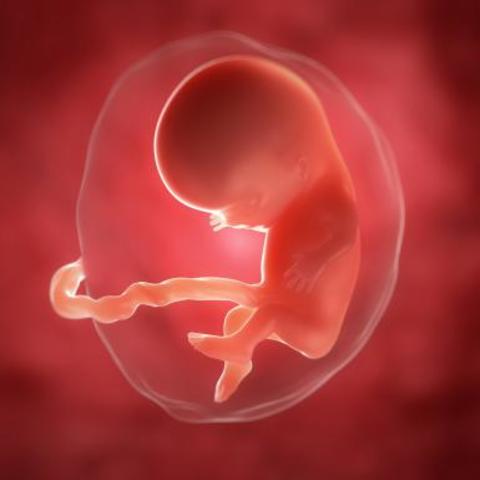

Las uñas y el pelo empiezan a crecer. Su médula y su hígado fabrican células sanguíneas.

El esqueleto y todos los órganos internos están formados, y la mayoría de ellos están funcionando ya. El embrión mide aproximadamente 10 cm y pesa casi 40 g.

A medida que su sistema nervioso madura, aparecen igualmente sus primeros reflejos.

La placenta funciona como un regulador del calor, manteniendo constante la temperatura de la sangre.

El sexo del bebé ya es visible.